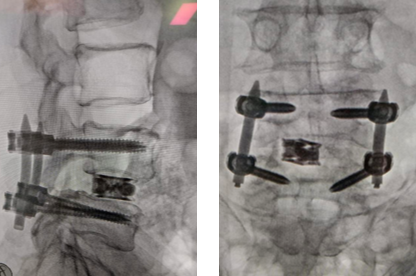

After Surgery Results

The surgeon removes the damaged disc or diseased bone, places a cage or bone graft between the vertebrae, and secures it with screws and rods. Over months, the bones heal together naturally. The surgical approach (front, back, or side) depends on the patient's specific condition and body type.